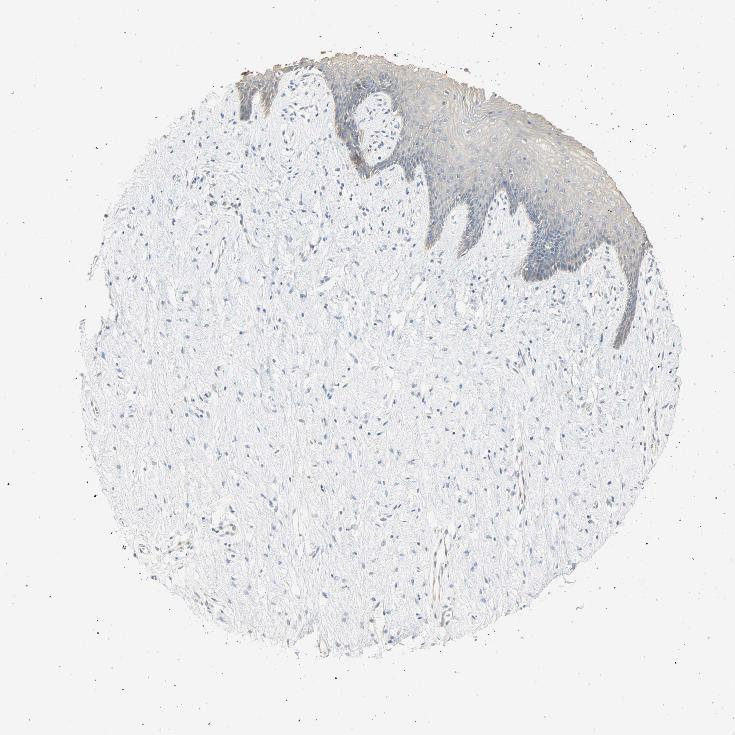

VAGINA - Antibody stainingi

Antibody staining in the annotated cell types in the current human tissue is reported as not detected, low, medium, or high, based on conventional immunohistochemistry profiling in selected tissues. This score is based on the combination of the staining intensity and fraction of stained cells.

Each image is clickable and will lead to virtual microscopy that enables deeper exploration of all samples and also displays staining intensity scores, fraction scores and subcellular localization as well as patient and tissue information for each sample.

Antibody HPA004827

Squamous epithelial cells Low